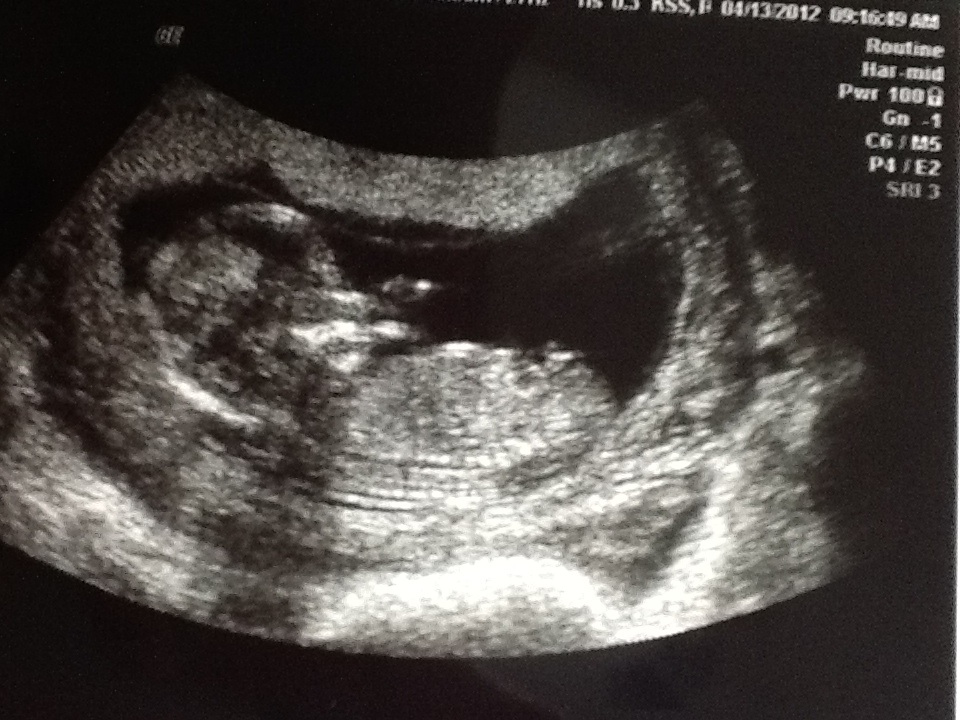

13 weeks and 0 days nub shots, tell me what you think!

bottom one does look more pink than blue, and no nub in the top pic!

Looks girlie from second pic. But not the best shots.....